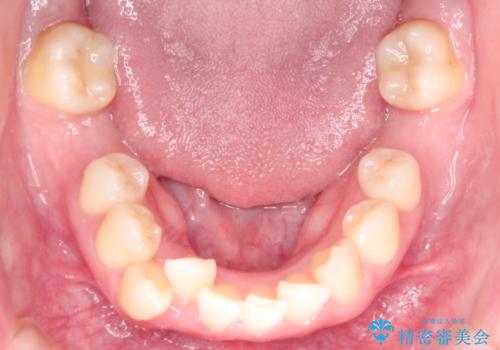

- 患者様は、下顎両側の第1大臼歯(6番)と右上6番の欠損を主訴に来院されました。

通常であればインプラントによる補綴が第一選択となる症例でしたが、患者様ご自身がインプラントを希望されなかったため、矯正治療によって欠損部の閉鎖を図る方針としました。

同時に、親知らず(智歯)の萌出や位置も考慮し、咬合全体のバランスを改善する矯正治療計画を立案しました。